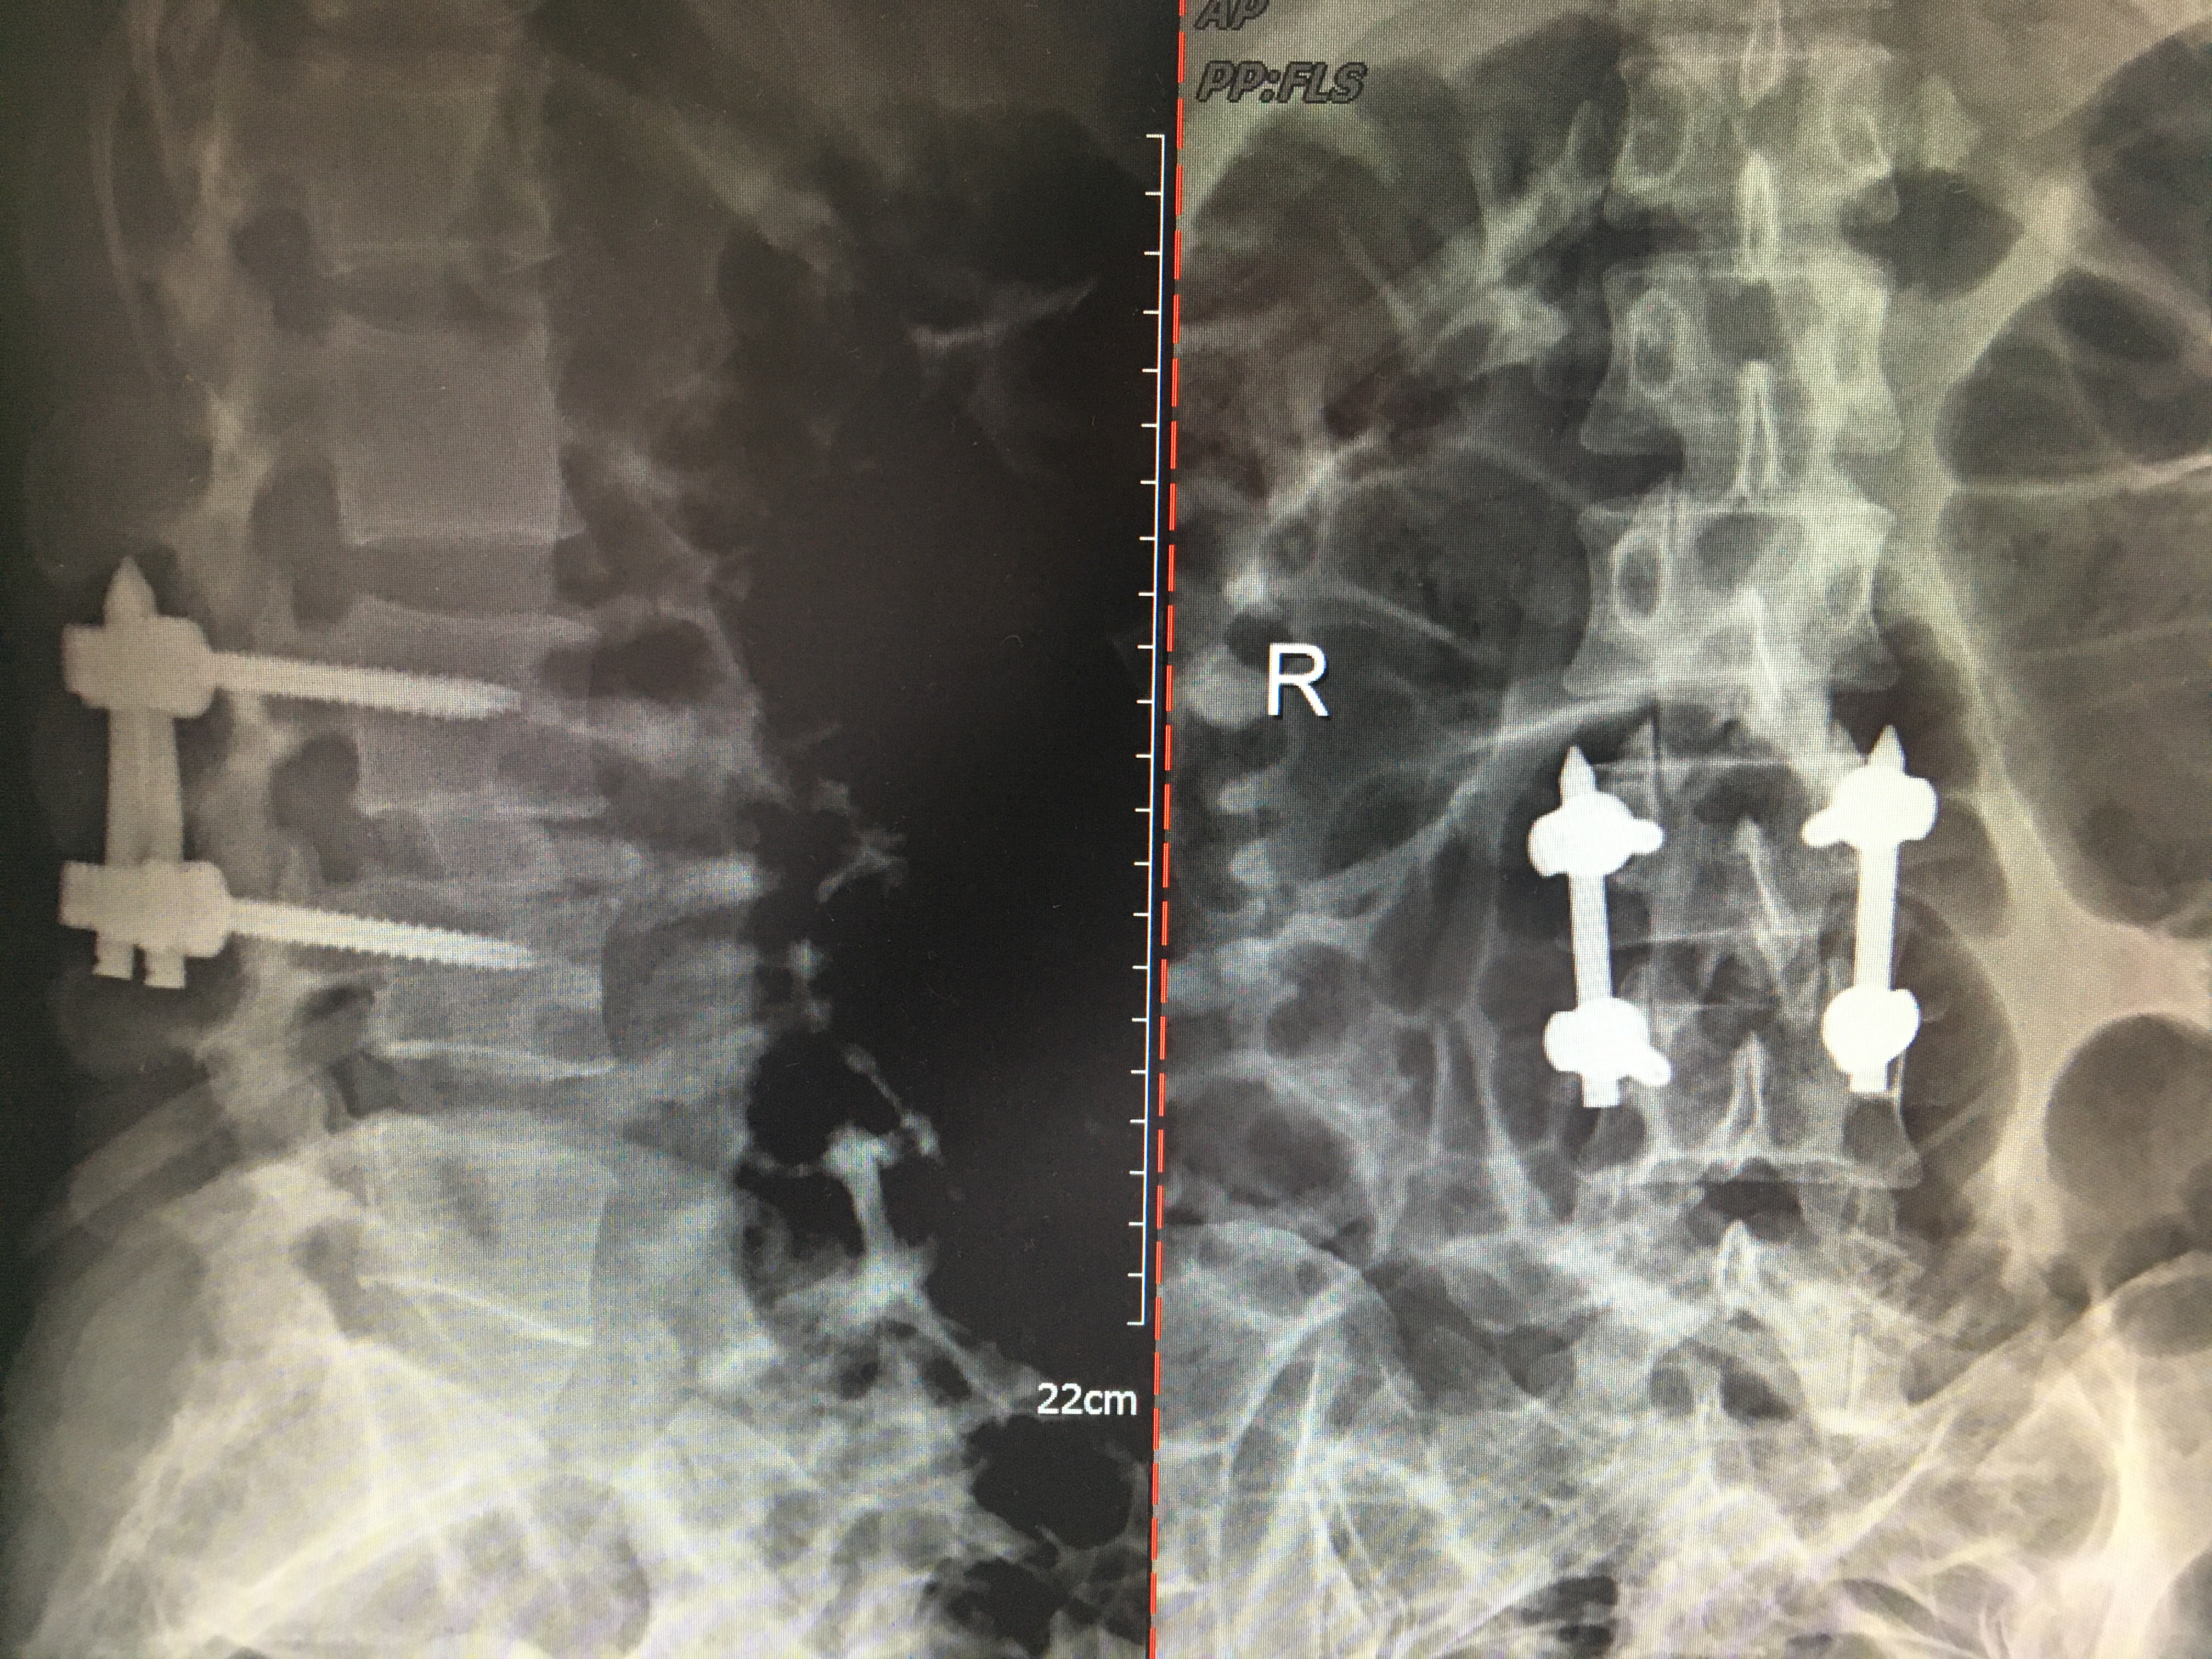

术后X线

术后第2天,陈姐能佩戴支具下地行走。根据术中提取的组织做涂片及培养后确定为化脓性脊柱炎(腰3-4):戈登链球菌感染。腰椎感染原因明确了,这下陈姐治疗用药终于有了科学依据。2周后,陈姐手术伤口愈合了,腰板变直了,人也变美了。